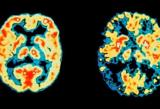

Երկու նոր դեղ, որոնք նախատեսված են ուշ փուլում երիկամի քաղցկեղով հիվանդների համար, կարող են արմատապես փոխել նրանց բուժումը՝ պնդում է Եվրոպական ուռուցքաբանական կենտրոնը (ECC): Այս մասին գրում է BBC-ն:

Երկու դեղն էլ բարձրացնում են ողջ մնալու գործակիցը՝ վկայում են ուսումնասիրության արդյունքները:

Դեղերից մեկն ակտիվացնում է մարդու իմունային համակարգը, իսկ երկրորդը ճնշում է ազդակները, որոնք առաջացնում են ուռուցքում բջիջների անվերահսկելի կիսում:

Նշենք, որ երիկամի քաղցկեղը Մեծ Բրիտանիայում տարածվածությամբ 8-րդն է: Այս հիվանդության պատճառով մարդիկ մահանում են հատկապես դրա ուշ փուլերում: